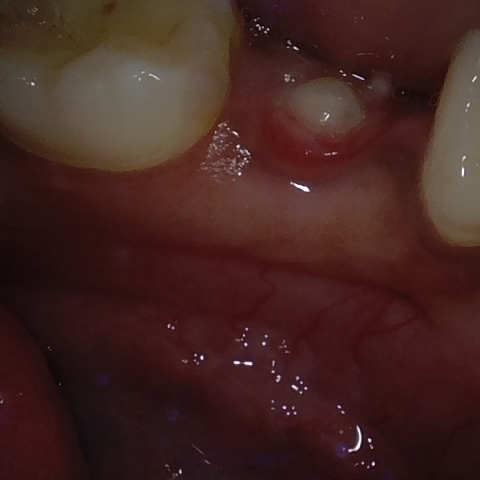

Annotated as "Good"